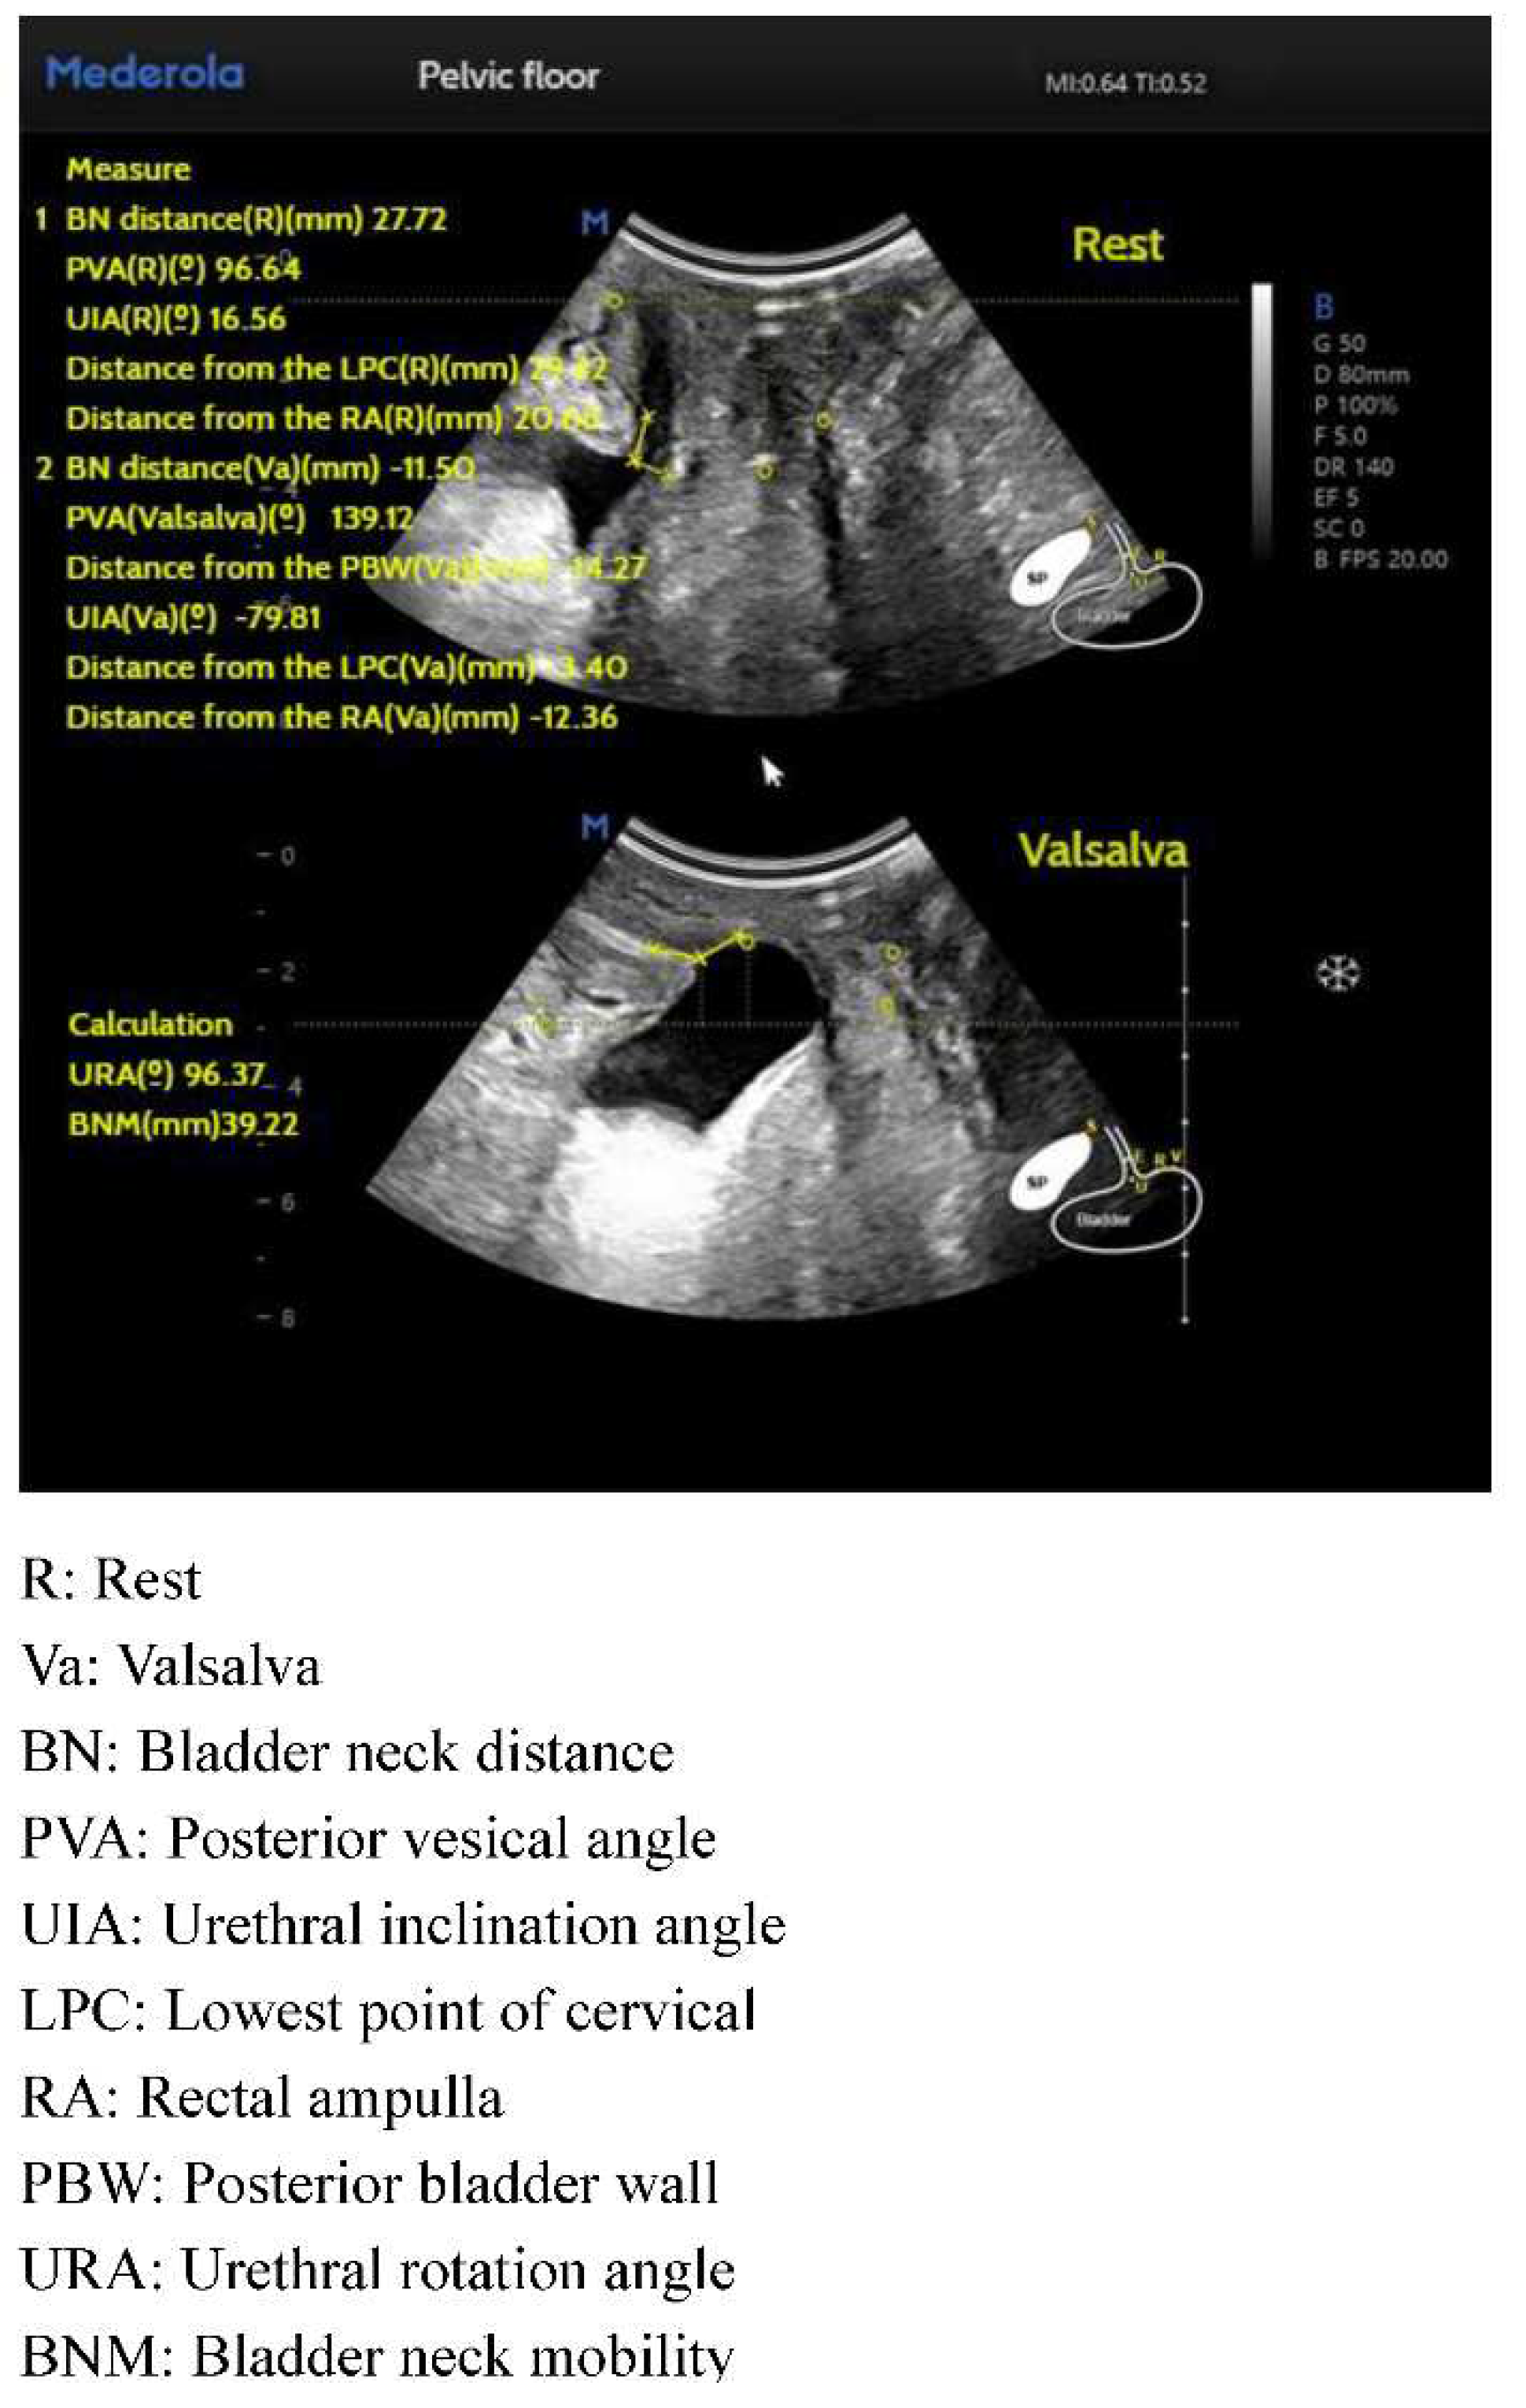

Conventional pelvic floor ultrasound assessment of female pelvic floor structure and function relies on the three dimensions of pelvic floor median sagittal section at maximal Valsalva state, tomographic ultrasound imaging of the anal raphe and anal sphincter and anal raphe fissure at maximal Valsalva state; however, the manual identification is highly empirically dependent, and AI automated identification and measurement can reduce the empirical dependence of the manual identification. The software/algorithms are used to extract features from the labeled images to enable automatic computer recognition. Currently, AI can be used in ultrasound applications to automatically measure and recognize some of the data of pelvic floor structures. For example, in anterior pelvic measurement, the main parameters of the bladder neck in the resting state, including bladder neck distance, bladder posterior angle, urethral inclination angle, etc., are automatically measured, and the above parameters are measured synchronously in the Valsalva state, so as to calculate the angle of rotation of the urethra and the degree of movement of the bladder meridian, etc., and to automatically obtain the bladder bulge and the biological indicators related to stress incontinence, so as to reduce the reliance on the operator’s experience, and to obtain the standardized section and measurement value quickly. The standardized cut surface and measurement value can be obtained quickly by reducing the operator’s experience. (Figure 2). For the anorectal fissure, biological measurements of anorectal fissure dilatation and anorectal muscle damage were automatically obtained by localizing the level of the anorectal fissure in the maximal Valsalva state (Figure 3). For automatic localization of the TUI tomography of the anal retinaculum muscle, operator experience dependence was reduced, and standardized views of the integrity of the anal retinaculum fissure were automatically obtained (Figure 4). Automatically obtained parameters of interest include bladder neck mobility, anal reticulum fissure, urethral rotation angle, and posterior vesicourethral angle, which greatly reduces measurement discrepancies due to physician experience.

Traditional pelvic floor ultrasound requires a high degree of professionalism on the part of the operator. Pelvic floor ultrasound based on the core algorithm of Artificial Intelligence (AI) can simulate the real ultrasound doctor’s pelvic floor related index measurement path and logic, summarize the huge amount of big data, and integrate the cloud computing logic into the pelvic floor intelligent medical care, and there are pelvic floor ultrasound that can realize automatic measurement of the distance from the neck of the bladder, the bladder posterior angle, the distance of the posterior wall of the bladder, the angle of inclination of the urethra, the angle of rotation of the urethra, urethral mobility and other indicators, providing intelligent measurements for the clinical diagnosis of lower urinary tract symptoms and improving the efficiency and level of diagnosis and treatment.

Posterior vesicourethral angle, funneling, urethral rotation angle, and bladder neck mobility are routinely observed in pelvic floor ultrasound in patients with urinary incontinence, and it has been shown that pelvic floor ultrasound can be used for transperineal ultrasound of the urethral rotation angle, the position of the bladder neck in the maximum Valsalva state, and the bladder neck mobility have high value in the diagnosis of female stress incontinence, which can help in the diagnosis and assessment of stress incontinence [67], and it also can be used to assess urinary incontinence, voiding abnormalities, and periurethral lesions.3D/4D ultrasound is used to visualize urethral mobility, which increases after delivery, especially after instrumental assisted delivery, indicating a change in urethral support [68]. Ultrasound is the method of choice for residual urine volume determination [40], and whether the residual urine volume exceeds 100 mL is used as one of the indicators for observation of uncomplicated and complicated stress urinary incontinence, and preoperative and postoperative residual urine volume can be examined by catheterization or pelvic floor ultrasound. In addition, ultrasound is the method of choice for diagnosing postoperative complications such as postoperative urge incontinence, bladder dysfunction, and sling position. Post-colonoscopy ultrasound ultrasound imaging can be used to show bladder stability behind the neck of the sling.